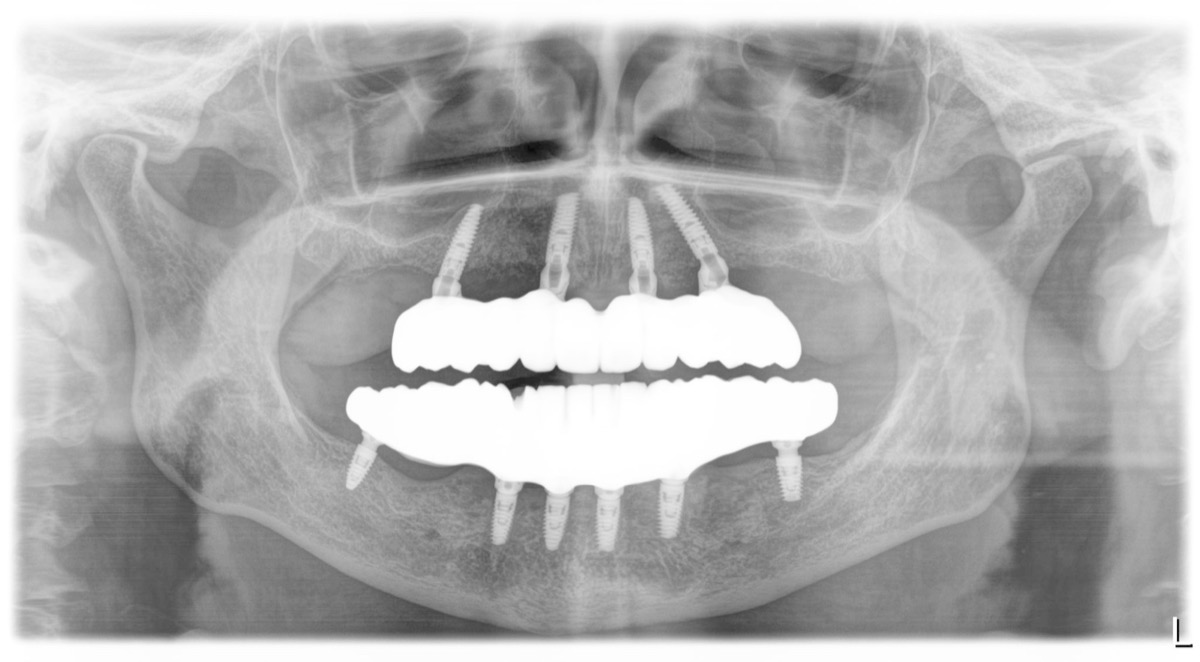

All-on-4 to innowacyjna technika protetyki stomatologicznej, która umożliwia pacjentom z utratą wielu zębów, a nawet całkowicie bezzębnym, uzyskanie stałego i stabilnego uśmiechu w ciągu jednej wizyty. Metoda polega na zamocowaniu całkowicie nowego łuku zębowego na czterech implantach zębowych. Co ważne, jeśli pozwala na to sytuacja kliniczna, implanty są umieszczane w miejscach o największej gęstości kości, co eliminuje konieczność wszczepiania dodatkowych implantów stomatologicznych czy przeszczepiania kości.

Dzięki cyfrowemu planowaniu opartemu o projekt uśmiechu, warunki zgryzowe pacjenta i badanie tomograficzne CBCT, zabieg implantacji jest wykonywany w sposób nawigowany. Lekarz wykorzystuje szablon implantologiczny, w którym wskazane jest idealne spozycjonowanie implantów. Oparta na czterech implantach praca protetyczna odtwarza prawidłowy zgryz pacjenta.

Z punktu widzenia okluzji czyli zgryzu, u pacjenta bezzębnego lub takiego, u którego usuwamy wszystkie zęby, wykonanie dobudowy górnego i dolnego łuku zębowego w jednym czasie jest najlepszym rozwiązaniem. Nowy uśmiech planuje się tak, aby odtworzył idealne, prawidłowe warunki zgryzowe u danego pacjenta. Mówiąc najprościej; nie trzeba dopasowywać prawidłowej góry do nieprawidłowego dołu i odwrotnie.

Po około 3 miesiącach gojenia oraz kontrolnym badaniu RTG (np. tomografii komputerowej CBCT) wykonuje się pracę ostateczną, obejmującą 10 lub 12 koron na implantach. Koszt finalnej rekonstrukcji wynosi od 33 000 zł – cena zależy od zastosowanych materiałów, komponentów protetycznych oraz ilości koron w łuku zębowym.